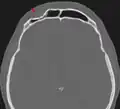

Impressionsbruch der Stirnhöhle in der Computertomographie (Pfeil). Die hintere Stirnhöhlenwand zum Hirnschädel ist hier nicht betroffen. -